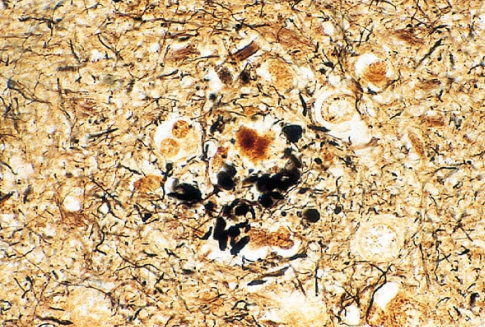

Bielschowsky 100 test - Special Stains

Product for the preparation of cyto-histological samples for optical microscopy. Recommended method to show neurofibrils, axons, dendrites and senile plaques in Alzheimer's disease.